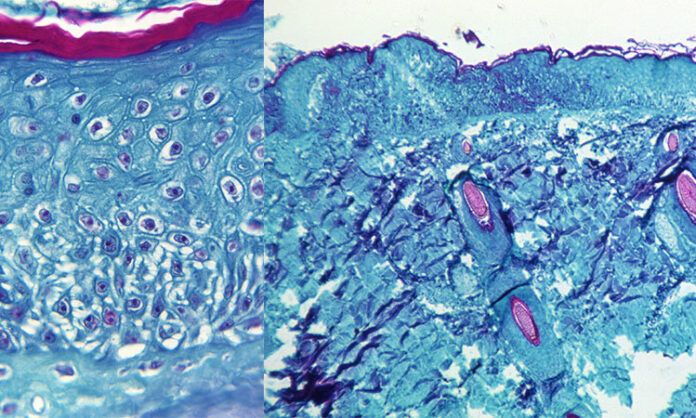

En el estudio, los investigadores utilizaron técnicas de espectrometría de masas y microscopía de superresolución para identificar y caracterizar la proteínas relevantes en el virus vaccinia, la vacuna contra la viruela, que es miembro de la misma familia de virus de la viruela símica y de la viruela humana.

Si bien todos los virus tienen el objetivo de invadir las células y replicarse con éxito, también deben encontrar formas de eludir el sistema inmunitario innato del cuerpo: las defensas de amplio espectro contra los patógenos invasores. En la mayoría de los virus, esto se produce mediante la producción de proteínas durante la replicación que pueden evadir y atacar al sistema inmunitario. Los virus de la viruela, por el contrario, son inusuales porque contienen y entregan proteínas inmunomoduladoras desde el principio.(Infobae)